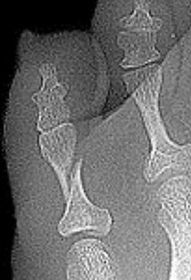

What disease is this? What is shown by A, B and C? | Psoriatic arthritis. A = destructive changes B = Pencil in cup deformity C = IPJ fusion |